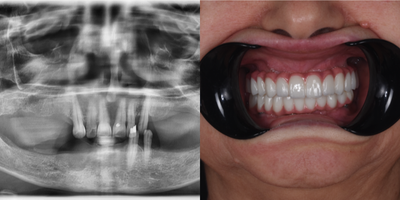

45-54 year old woman treated with All-on-4 Dental Implants, Dental Implants

All-on-4 for upper edentulous jaw and dental implants for partial edentulism in lower jaw has been performed 5 years ago. Our patient has quit smoking and there is no bone loss around implants in 5 years followup